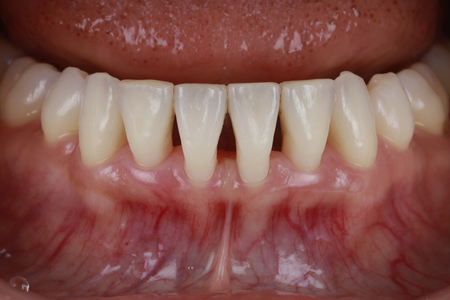

下がった歯茎を美しく、強く再生|

30代 男性

矯正治療と根面被覆術による口腔環境の改善

治療名 【審美・機能回復】歯肉退縮に対する根面被覆術+マウスピース矯正 治療期間 約1年 執刀医 Dr. 大杉 治療費 1,150,000円(税込)

オペ費用 250,000円治療解説 歯肉退縮の改善と、将来的に歯を失うリスクを下げる目的で治療を行いました。

まずマウスピース矯正で歯列と噛み合わせを整えたうえで、結合組織移植による根面被覆を実施。

見た目だけでなく、歯を長く残すための安定性も重視して回復を図りました。リスク・副作用 歯の移動時に数日程度の違和感や疼痛が生じることがあります。

術後の過度なブラッシング圧や不適切な清掃用具の使用は、再度の歯肉退縮(再発)を招く主原因となるため、適切なケア指導の遵守が必要です。 -

Treatment selection歯ぐきが下がってしまった方へ

—— 根面被覆という治療選択

重度の歯周病では炎症を取り除いた後でも、歯ぐきが大きく後退した状態だけが残ってしまうことがあります。

歯ぐきの退縮は見た目の変化だけでなく、知覚過敏の悪化や歯根むし歯のリスク上昇、歯の動揺など、将来的なトラブルへ直結する重要なサインです。

医療法人大杉歯科医院では、歯周病治療で炎症を改善した後も、お口の機能を長く維持するために、歯ぐきを補強し歯根を守る「根面被覆(歯肉移植)」にも対応しています。

CTG・FGGによる歯肉移植で健康的な歯ぐきを再構築

根面被覆とは、歯周形成外科の一つで、後退した歯ぐきを回復させるための専門的な治療です。

薄く弱くなった歯ぐきを補強し、露出した歯根を再び覆うことで、審美性と機能性の両方を改善します。

CTG(結合組織移植術)

上あごの内側から「結合組織」を採取し、退縮した部分に移植する方法です。

歯ぐきに自然な厚みが生まれ、特に審美性が求められる前歯の治療に適しています。 -